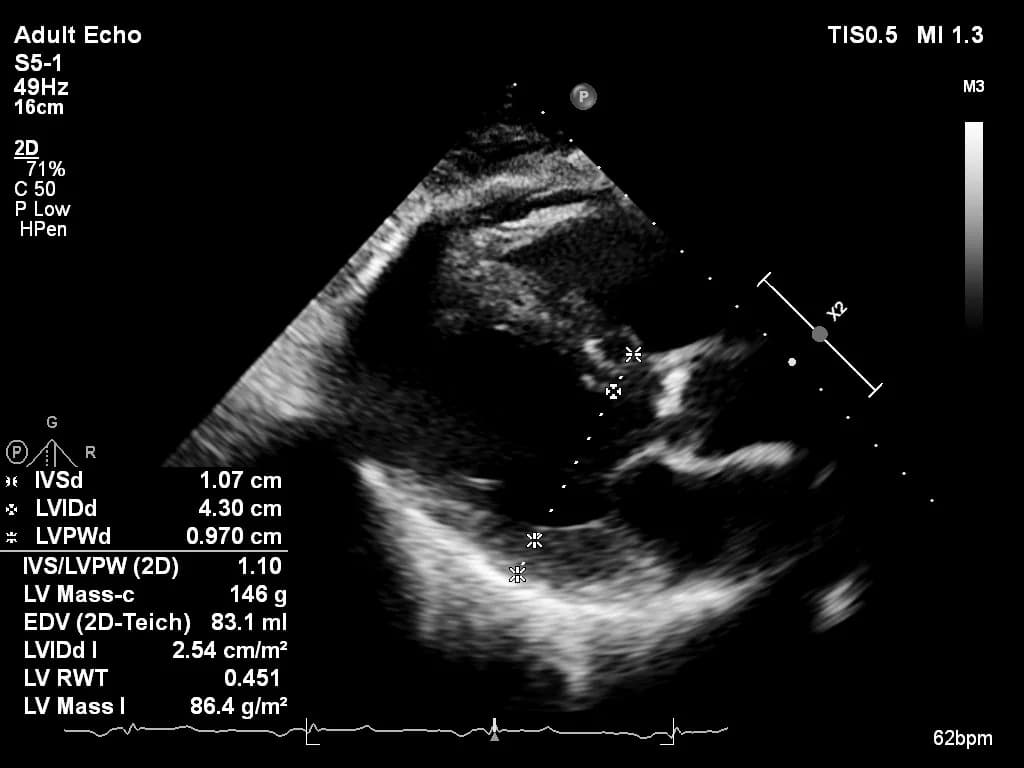

Practice with anonymized echocardiography cases from real clinical encounters.